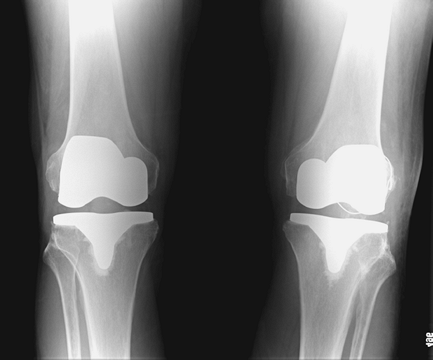

ultimately healed without an extension lag or quadriceps weakness (Figs. 26-2, 26-3, 26-4).

Figure 26-4 Anteroposterior view of bilateral total knee arthroplasties and healed left patella fracture.